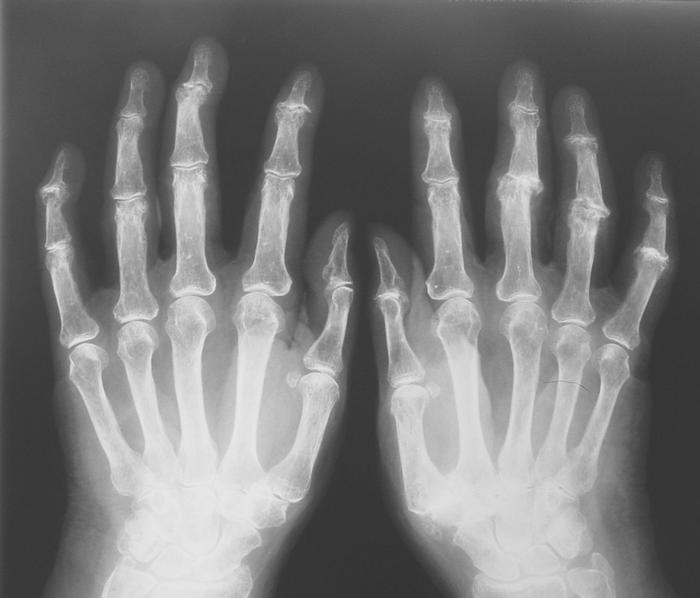

La osteoartritis es uno de los tipos de artritis más comunes en la actualidad. Esta enfermedad afecta a las articulaciones de los huesos, desgastando y rompiendo la capa superior de los cartílagos que recubren las articulaciones. Como resultado la persona experimenta dolor, inflamación, hinchazón y pérdida de movimiento en la articulación, pudiendo en los casos más graves perder el aspecto normal de la articulación.